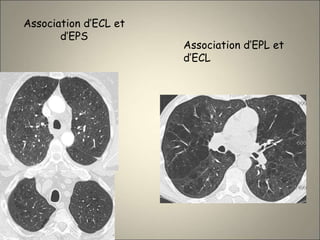

Association d’ECL et

d’EPS

Association d’EPL et

d’ECL